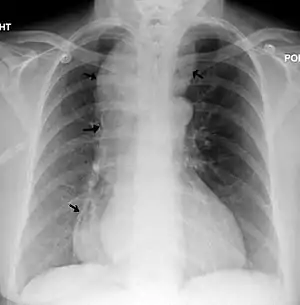

![]() | |

| A chest X-ray showing achalasia ( arrows point to the outline of the massively dilated esophagus ) | |